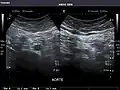

Aorta: Visualized portions normal in caliber, 16 x 15 mm.

Standard measurement of the abdominal aorta[4]

It can be used on the abdominal aorta to detect or exclude abdominal aortic aneurysm. For this purpose, the standard aortic measurement for abdominal aortic aneurysm is between the outer margins of the aortic wall.[4]